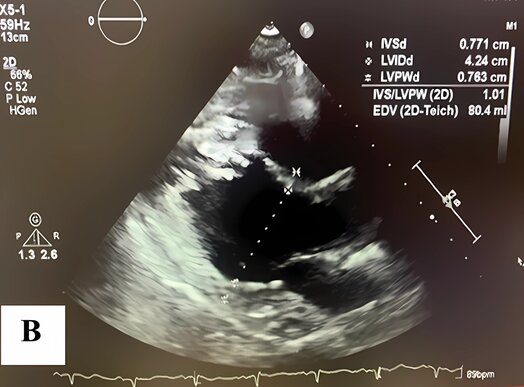

A follow-up transthoracic echocardiogram, performed approximately two months after discharge, revealed complete normalization of left ventricular systolic function, with an estimated ejection fraction of 70–75%. There were no regional wall motion abnormalities, and only mild grade I diastolic dysfunction persisted (average E/e′ = 11). Trivial pericardial effusion and a small residual left pleural effusion were present. Additionally, mild mitral valve leaflet calcification was observed without stenosis or regurgitation (Figure 6(a) and (b)). These findings confirmed full recovery from Takotsubo cardiomyopathy and complete resolution of the apical thrombus. The patient remained clinically stable with no recurrence of symptoms during follow-up.

Figure 6. A follow-up transthoracic echocardiogram was performed approximately two months after discharge.

(A) Systolic and (B) Diastolic images show complete normalization of left ventricular function, with resolution of apical ballooning and absence of thrombus.